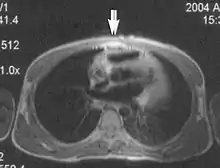

Metal artifacts occur at interfaces of tissues with different magnetic susceptibilities, which cause local magnetic fields to distort the external magnetic field. This distortion changes the precession frequency in the tissue leading to spatial mismapping of information. The degree of distortion depends on the type of metal (stainless steel having a greater distorting effect than titanium alloy), the type of interface (most striking effect at soft tissue-metal interfaces), pulse sequence and imaging parameters. Metal artifacts are caused by external ferromagnetics such as cobalt containing make-up, internal ferromagnetics such as surgical clips, spinal hardware and other orthopaedic devices, and in some cases, metallic objects swallowed by people with pica.[3] Manifestation of these artifacts is variable, including total signal loss, peripheral high signal and image distortion (Figs 3 and 4).[1] Reduction of these artifacts can be attempted by orientating the long axis of an implant or device parallel to the long axis of the external magnetic field, possible with mobile extremity imaging and an open magnet. Further methods used are choosing the appropriate frequency encoding direction, since metal artifacts are most pronounced in this direction, using smaller voxel sizes, fast imaging sequences, increased readout bandwidth and avoiding gradient-echo imaging when metal is present. A technique called MARS (metal artifact reduction sequence) applies an additional gradient, along the slice select gradient at the time the frequency encoding gradient is applied. ==Signal processing dependent artifacts== The ways in which the data are sampled, processed and mapped out on the image matrix manifest these artifacts.[1]